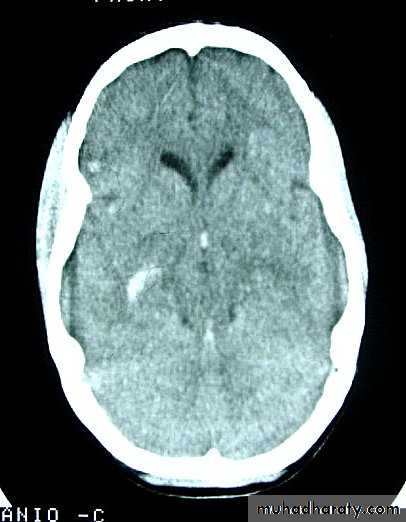

1. Diffuse Axonal Injury

Prolonged post-traumatic state in which there is loss of consciousness from the time of injury that continues beyond 6 hours.Occurs as a result of mechanical shearing at the grey-white matter interface.

This causes disruption and tearing of axons, myelin sheaths and blood capillaries.

Severity can range from mild damage with confusion to coma and even death.